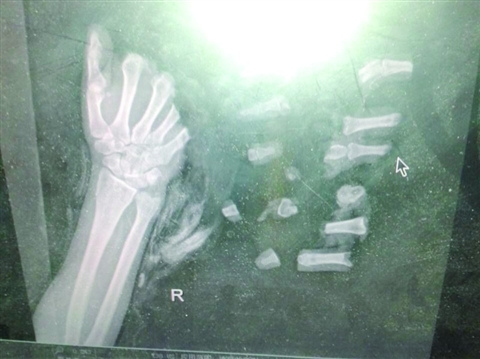

从这张X光片上可以看出,这只手掌上的五根指头完全断开,而每一截断掉的指头,又都分成了两到三截。是什么样的意外,造成了这样的伤害?前天,一位21岁的花样少女竟然遭遇横祸,右手手指被绞断成13截。

从前天上午12点开始,护士们先把13截断指一一从纱布里找出来,并放入冷藏箱内。三组医生同时进行断指衔接,除了中间换着吃饭,没有人休息。“断指伤口缝合,神经吻合度最关键,断指越多,神经通畅率越低,三组工作人员进度必须保持准确沟通、高度协作。”

由于破损严重,手术进行了15小时,一直做到昨日清晨。